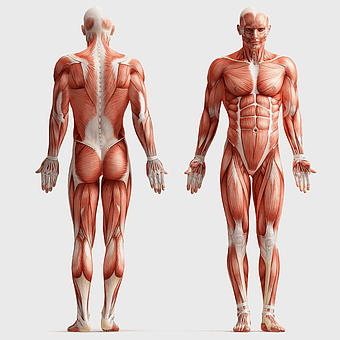

human anatomy diagram, muscular system illustration, human body muscles, fitness anatomy chart, skeletal muscle structure, human physiology study, muscle group analysis -

muscular system illustration, human anatomy diagram, fitness professional figure, skeletal muscle structure, muscular development, human body musculature, anatomical study -

human anatomy back muscles, male muscle structure, human anatomy illustration, man anatomy diagram, anatomical muscle chart, full-body muscle map, posterior muscle view -

human muscular system anatomy, fitness professional bodybuilder, human body organ systems, skeletal muscle tissue, full-body muscle diagram, anatomical muscle structure, human physiology illustration -

human muscular system illustration, muscle anatomy human body, fitness professional bodybuilder, human back and abdomen muscles, anatomical muscle structure, human skeletal muscle system, detailed human muscle chart -